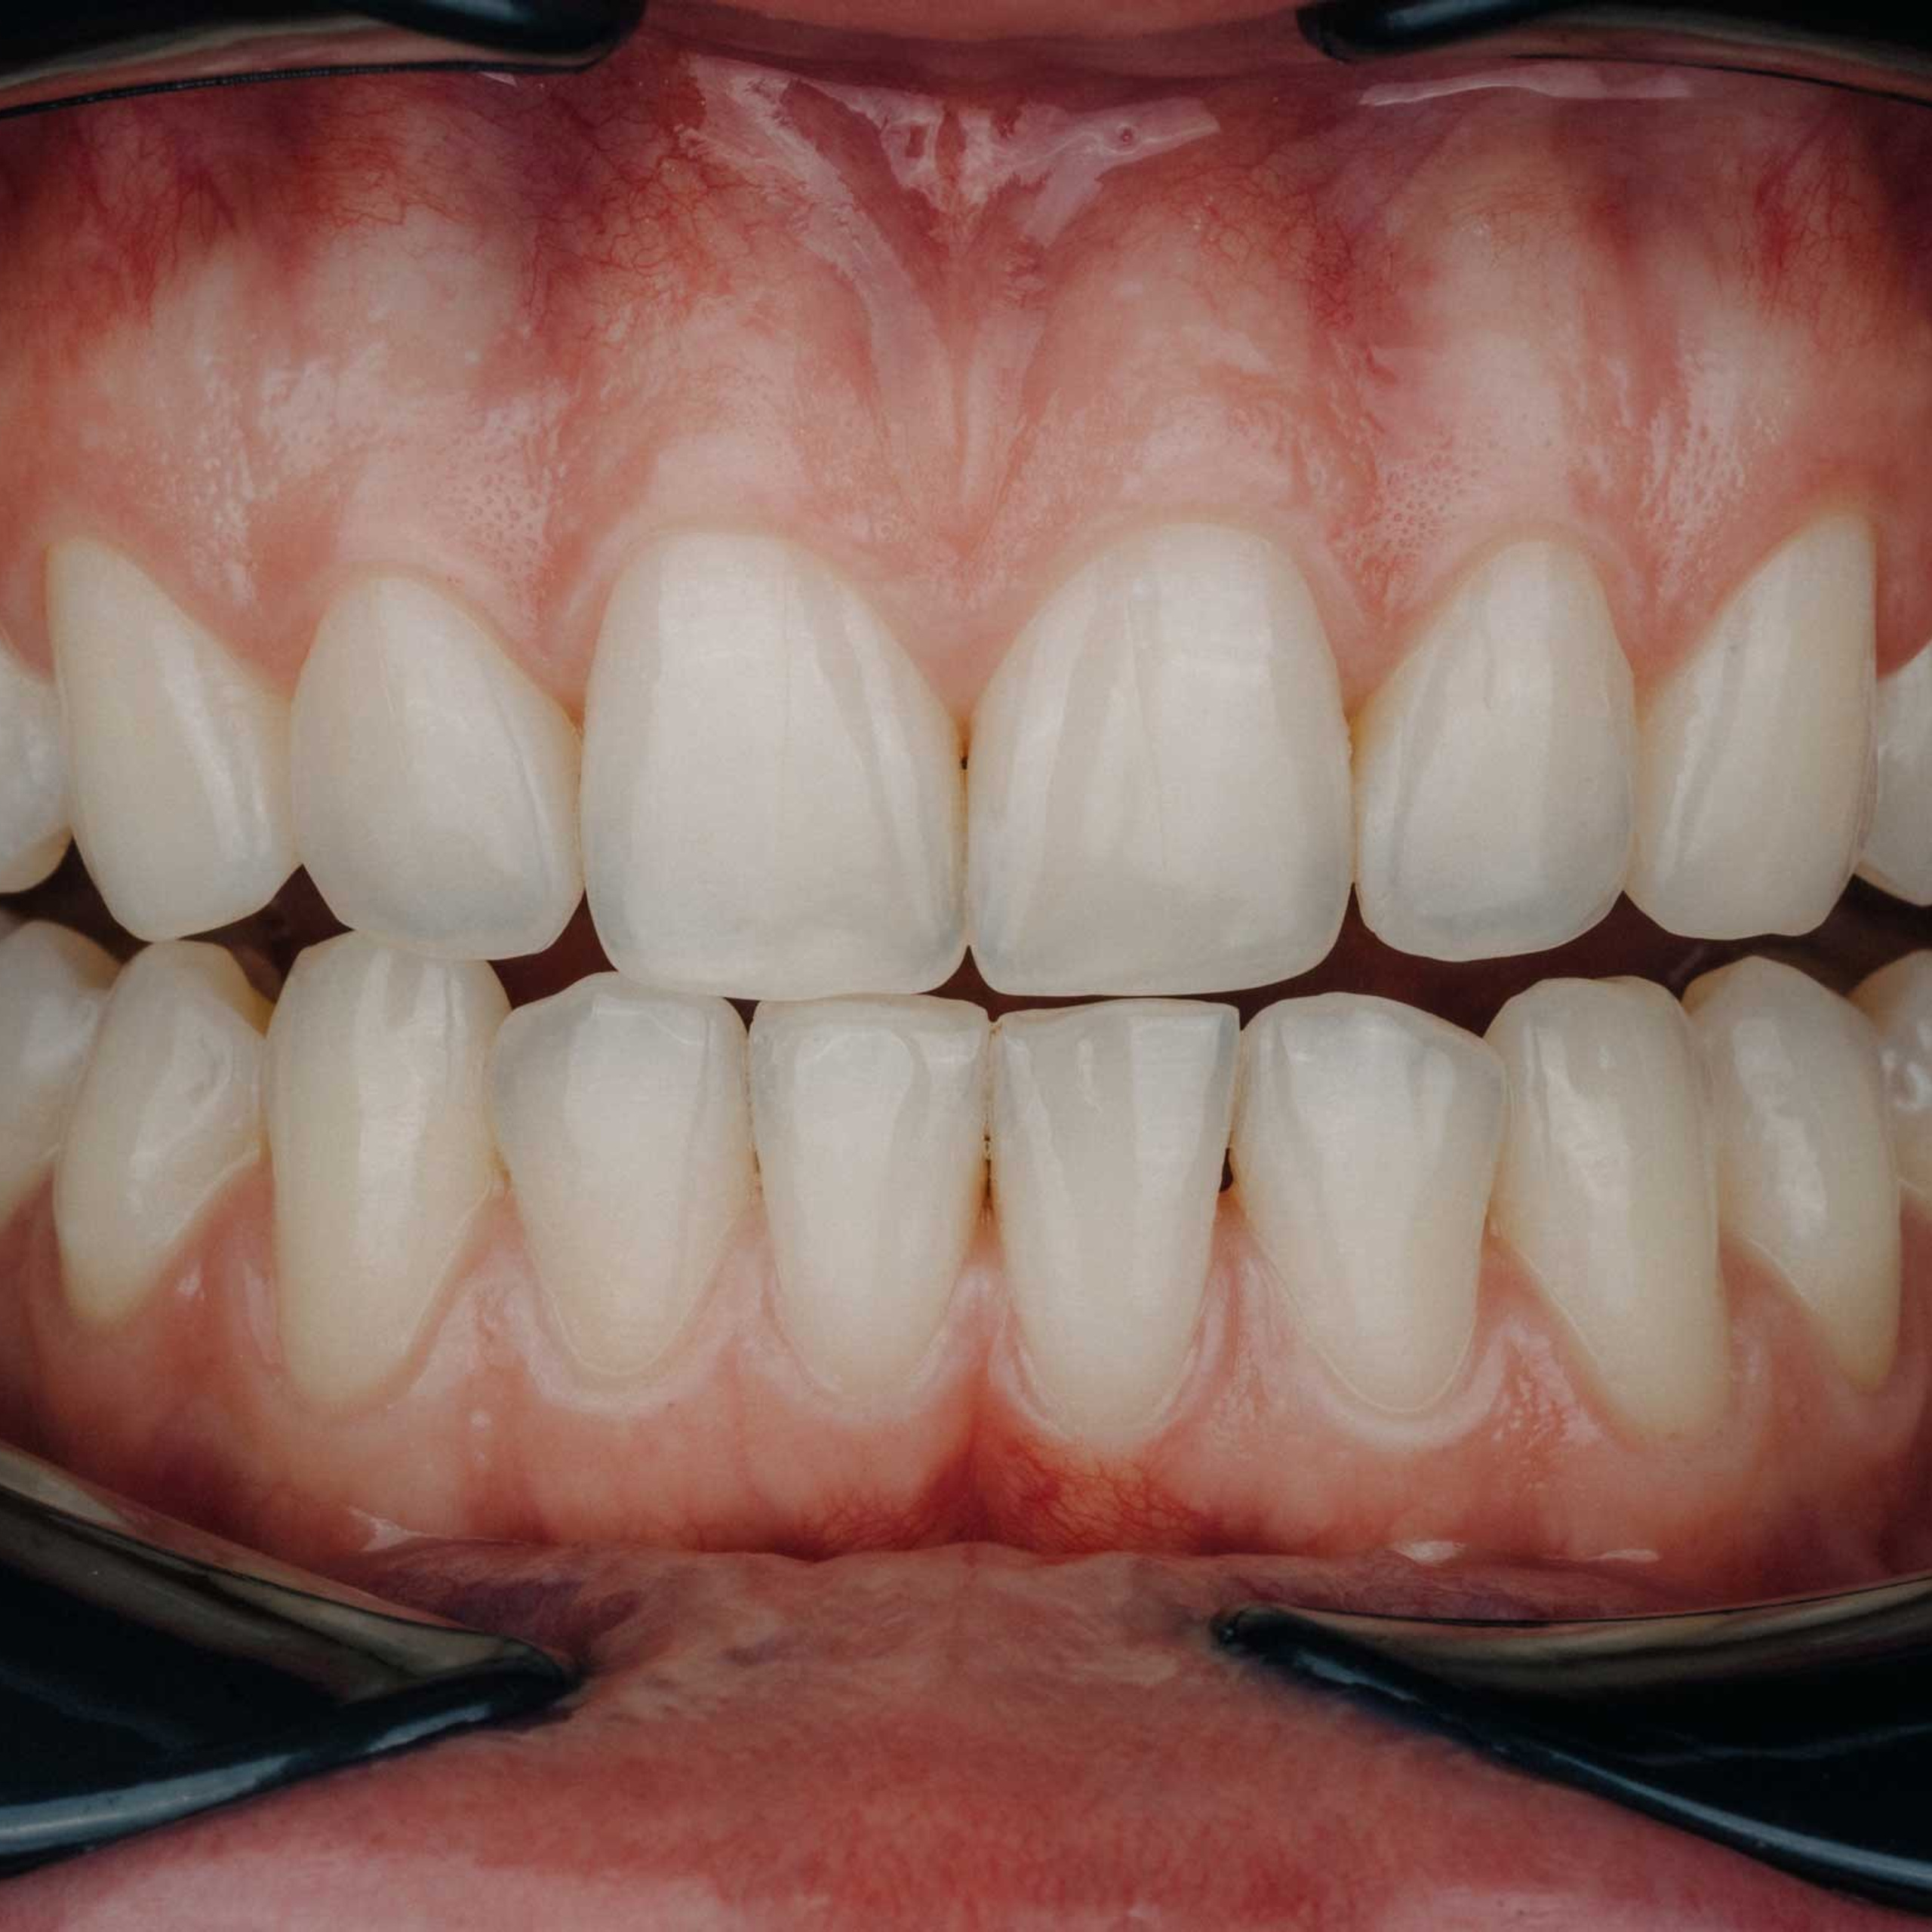

Фотографии учеников до обучения

Фотографии после обучения